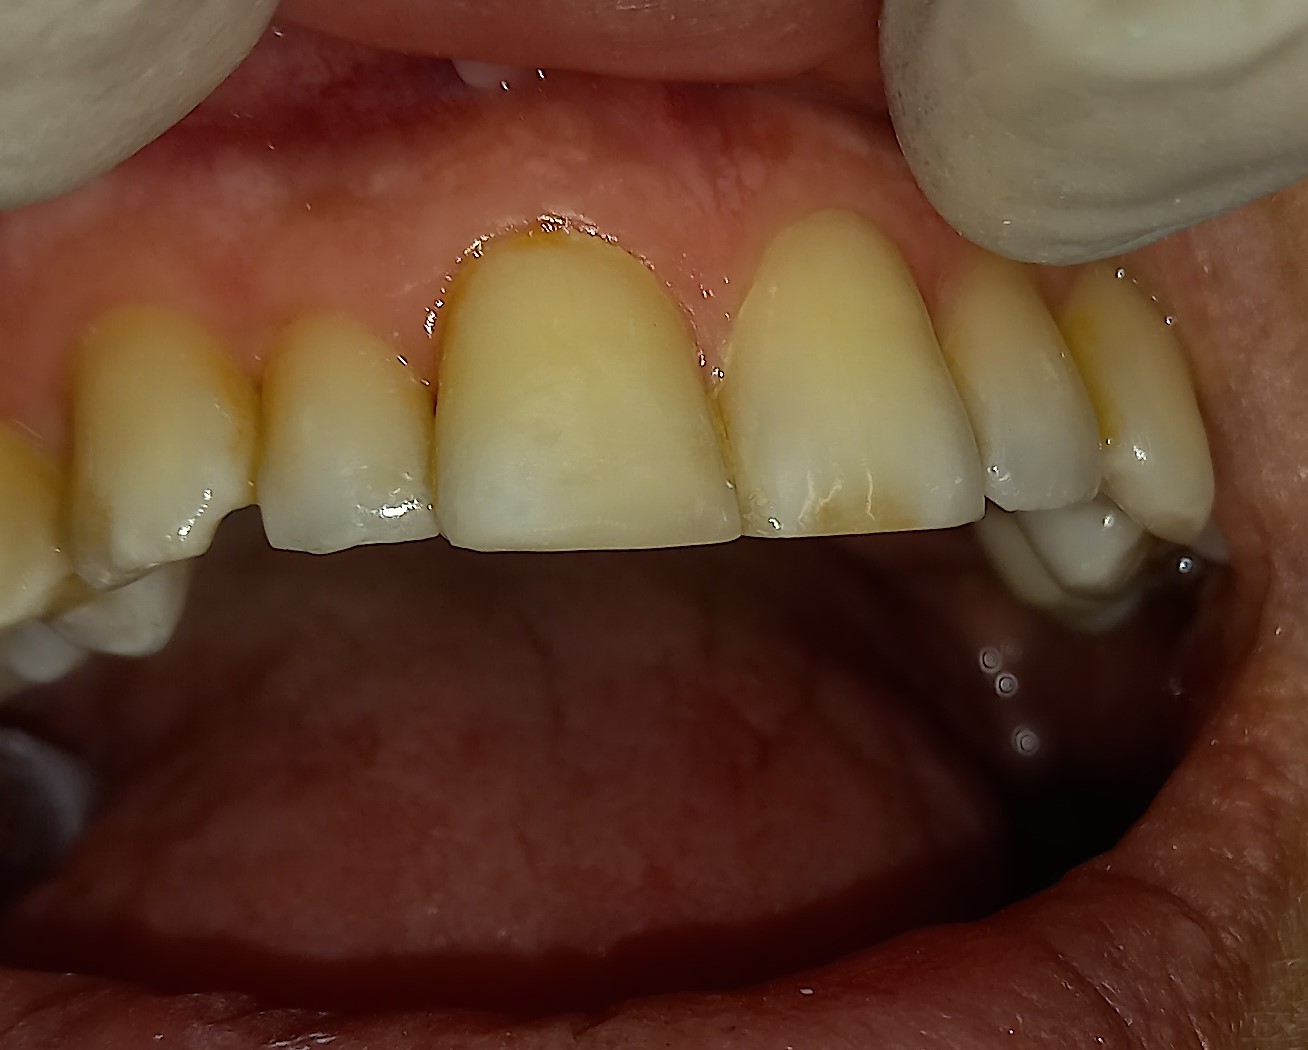

Επανάληψη απονεύρωσης σε τρία άνω πρόσθια δόντια